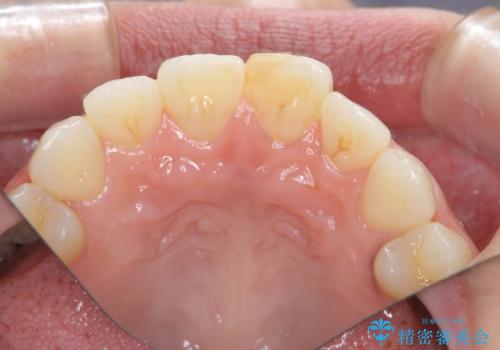

すり減った前歯の形態回復

- すり減ってしまった前歯の審美性の回復を希望され来院されました。

何度かレジン修復を試みたものの、脱離しやすく変色も気になる、とのことでセラミッククラウンによる審美性の回復を計画します。

右側は、クラウンにせず可及的に形態を整えることのみでの対応としました。